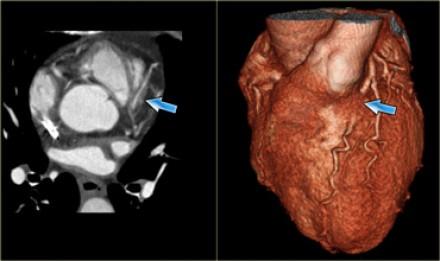

Myocardical bridging of the LAD (left anterior descending) coronary artery

CTA (computed tomography angiography) is currently the gold standard for evaluating myocardial bridging, because it‘s highly accurate. However, recent research has shown that CTA is not all-seeing and all-knowing. IVUS (intravascular ultrasound) may be the better choice.